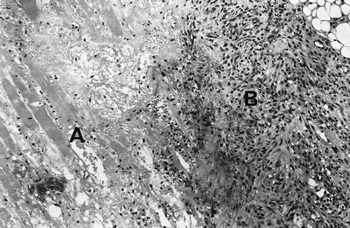

Investigations showed an elevated white cell count of 16 x 109/L (NR, 4.0–11.0 x 109/L), a platelet count of 432 x 109/L (NR, 150–400 x 109/L), an erythrocyte sedimentation rate of 110 mm/h (NR, 7–18 mm/h) and a C-reactive protein level of 119.3 mg/L (NR, 1.6–8.7 mg/L). Creatine kinase (174 U/L; NR, < 215 U/L) and lactate (0.6 mmol/L; NR, 0.5–2.0 mmol/L) levels were normal. Separate to the swelling on the medial aspect of the thigh, a presumed thrombus was palpable in the lateral accessory long saphenous vein. A subsequent ultrasound detected this thrombus extending from the mid thigh to the lateral aspect of the knee, but no deep venous thrombosis was found. She was treated with cephalexin and aspirin. Over the next two weeks, the thigh swelling evolved into a tender, palpable mass measuring 6 x 20 cm. A computed tomography (CT) scan revealed marked swelling of the entire adductor muscle group, but no discrete mass (Figure 1). In the absence of a clear diagnosis, an exploratory operation of her right thigh was performed. This showed no haemorrhage or abscess, but evidence of extensive oedema and necrosis of the adductor muscles. Samples taken for microbiological analysis were sterile. Histological examination of a biopsy specimen showed necrotic muscle, an inflammatory cell infiltrate, fibrosis and evidence of muscle fibre regeneration. The occasional small blood vessel containing fibrin thrombus was also seen, but no features of vasculitis were identified (Figures 2 and 3). A diagnosis of diabetic muscle infarction was made. ![]() ![]() Photomicrographs (original magnification x 250) of a biopsy specimen of the adductor group of muscles. Figure 2: Longitudinal section, showing necrotic muscle fibres (A) and granulomatous tissue (B). Figure 3: Cross-section showing necrotic muscle (A), an inflammatory cell infiltrate (B) and a blood vessel containing a thrombus (C). No evidence of vasculitis was seen. |